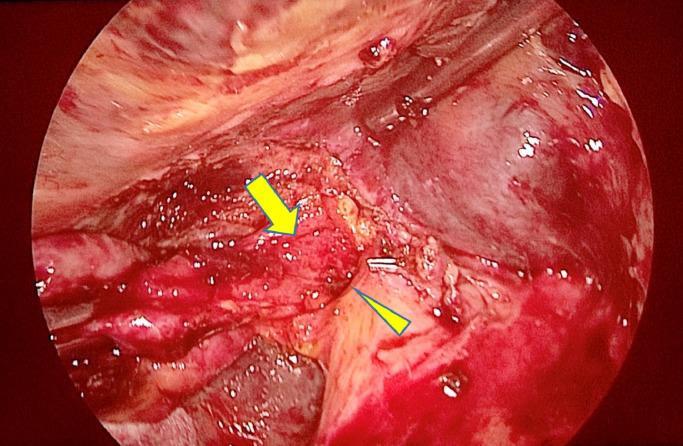

Mirizzi syndrome is a rare chronic cholecystitis complication. However, the current consensus on managing this condition remains controversial, especially through laparoscopic surgery. This report describes the feasibility of treating type I Mirizzi syndrome with laparoscopic subtotal cholecystectomy and electrohydraulic lithotripsic gallstone removal. A 53-year-old woman presented with dark urine and right upper quadrant pain for 1 month. On examination, she was jaundiced. Blood tests showed highly elevated liver and biliary enzyme levels. Abdominal ultrasound showed a slightly dilated common bile duct with suspicion of choledocholithiasis. However, endoscopic retrograde cholangiopancreatography showed a narrowed common bile duct extrinsically compressed by a gallstone in the cystic duct, establishing a Mirizzi syndrome diagnosis. Elective laparoscopic cholecystectomy was planned. At operation, the trans-infundibulum approach was used since dissection around the cystic duct was difficult due to severe local inflammation of Calot's triangle. The gallbladder's neck was opened, and the stone was removed by lithotripsy via a flexible choledochoscope. Common bile duct exploration through the cystic duct was normal. The fundus and body of the gallbladder were resected, followed by T-tube drainage and suturing of the gallbladder's neck. The patient's postoperative clinical course was uneventful. Treating Mirizzi syndrome remains a major challenge for hepatobiliary specialists even with open surgery due to high complication rates, including bile duct injuries. Treatment is primarily to clear out the responsible stone and necrotic tissue. Due to advances in endoscopic surgery and equipment, subtotal cholecystectomy with laparoscopic gallstone extraction provides a safe and effective option for patients with Mirizzi syndrome. Laparoscopic subtotal cholecystectomy with electrohydraulic lithotripsy is a feasible and useful approach for treating Mirizzi syndrome that avoids iatrogenic bile duct injury.

Mirizzi综合征是一种罕见的慢性胆囊炎并发症。然而,目前对于该病症的治疗共识仍存在争议,尤其是通过腹腔镜手术治疗时。本报告描述了采用腹腔镜次全胆囊切除术及电液压碎石取石术治疗Ⅰ型Mirizzi综合征的可行性。一名53岁女性因尿色深及右上腹疼痛1个月前来就诊。检查发现她有黄疸。血液检查显示肝酶和胆酶水平显著升高。腹部超声显示胆总管轻度扩张,怀疑有胆总管结石。然而,内镜逆行胰胆管造影显示胆总管因胆囊管内结石而受到外在压迫变窄,从而确诊为Mirizzi综合征。计划进行择期腹腔镜胆囊切除术。手术中,由于胆囊三角区严重局部炎症,难以在胆囊管周围进行解剖,因此采用经胆囊漏斗部入路。打开胆囊颈部,通过可弯曲的胆总管镜用碎石术取出结石。经胆囊管探查胆总管正常。切除胆囊底部和体部,随后放置T管引流并缝合胆囊颈部。患者术后临床过程顺利。即使是开放手术,治疗Mirizzi综合征对于肝胆专科医生来说仍是一项重大挑战,因为其并发症发生率高,包括胆管损伤。治疗主要是清除责任结石和坏死组织。由于内镜手术和设备的进步,腹腔镜胆囊取石次全胆囊切除术为Mirizzi综合征患者提供了一种安全有效的选择。腹腔镜次全胆囊切除术联合电液压碎石术是一种治疗Mirizzi综合征的可行且有用的方法,可避免医源性胆管损伤。